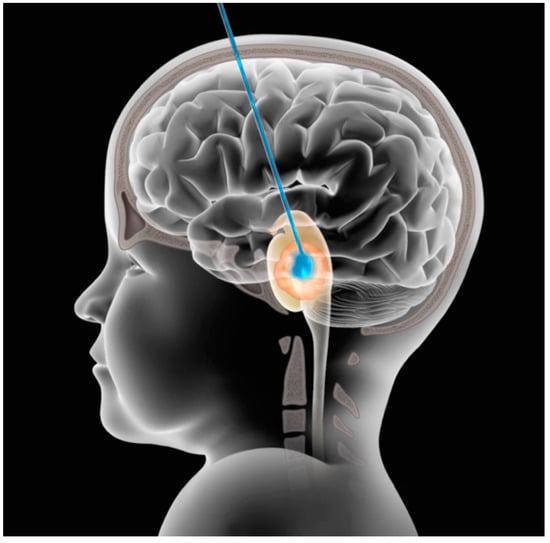

- Kuzan-Fischer, C.M.; Souweidane, M.M. The intersect of neurosurgery with diffuse intrinsic pontine glioma. J. Neurosurg. Pediatr. 2019, 24, 611–621. [Google Scholar] [CrossRef]